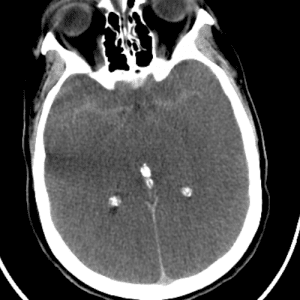

Arachnoid Granulation

Mimicking thrombus